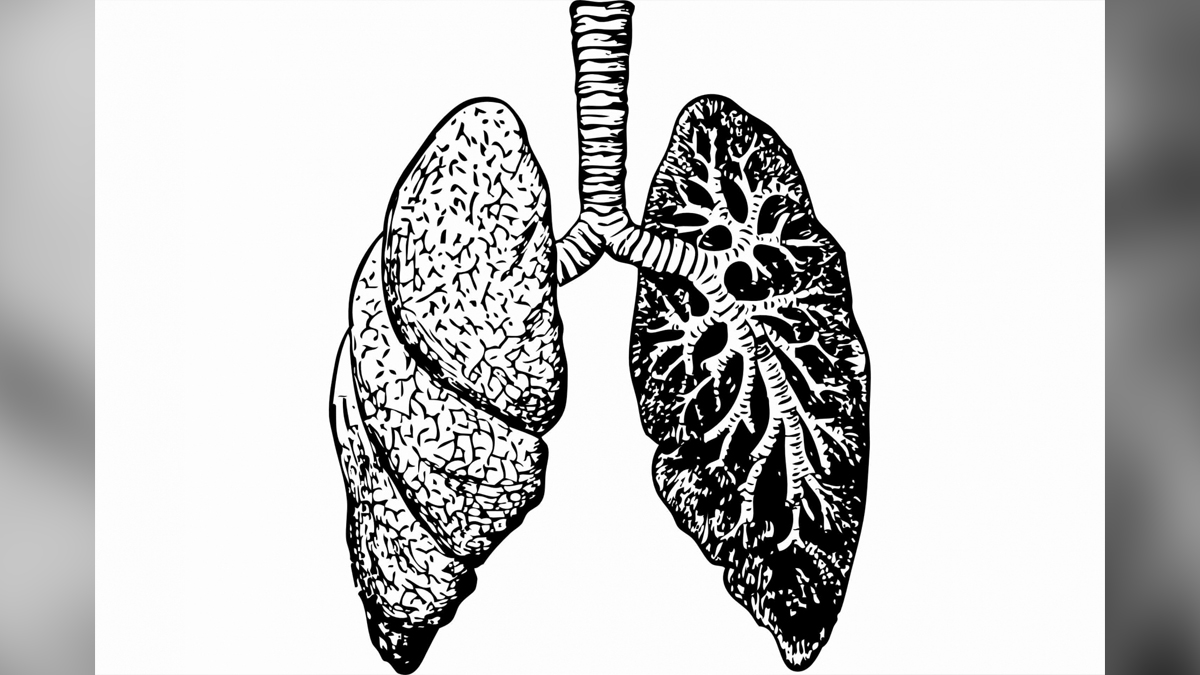

Lung Cancer: Prevalence and Statistics

Lung cancer is still a major global health concern, claiming millions of lives each year. Lung cancer was responsible for 2.2 million deaths in 2020, accounting for 13% of all cancer deaths worldwide, according to the World Health Organization (WHO). Lung cancer is predicted to impact 1.8% of the global population, with the highest proportion in North America, Europe, and East Asia.

Recent findings indicate that lung cancer incidence rates are gradually decreasing in some regions, owing primarily to successful anti-smoking campaigns and increased public consciousness about the risks of tobacco. However, in some areas, primarily in low and middle-income countries, the prevalence of lung cancer is still increasing, owing mainly to factors such as tobacco use and air pollution.

Unusual Early Signs and Symptoms of Lung Cancer

Early detection is critical for successful treatment of lung cancer and clinical outcomes. While persistent coughing, chest pain, and breathlessness are well-known symptoms, there are also several lesser-known early warning signs that people should be aware of:

The Role of Early Detection and Treatment

When it comes to lung cancer, early detection is everything. Regular screenings with imaging tests such as CT scans or X-rays can detect lung abnormalities before symptoms appear. Furthermore, biomarker testing allows doctors to identify specific mutations in lung cancer cells, enabling targeted therapies and personalised treatment plans.